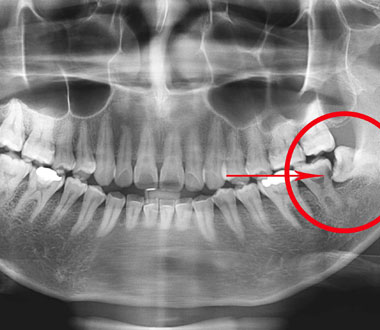

Oral and Maxillofacial Surgery

Tooth extractions